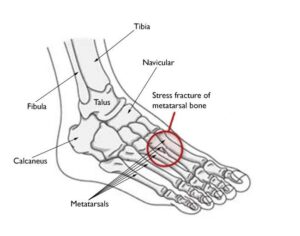

Stress fractures frequently affect the metatarsal bones in the foot and ankle, particularly:- Second and Third Metatarsals: These thinner, longer bones are more vulnerable due to the significant force exerted on them when pushing off during walking or running. Ballet dancers are particularly susceptible, as are individuals with a disproportionately larger second metatarsal bone. Pain is typically felt in the middle of the foot.

The most common sites for stress fractures in the foot are the metatarsal bones.